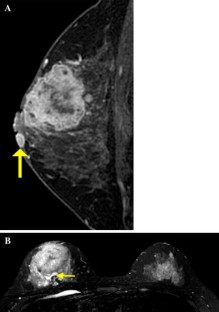

Fig. 1